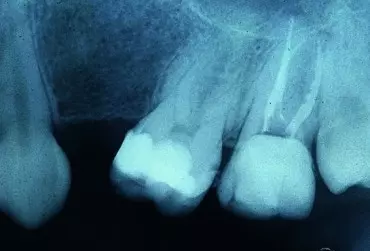

Przegląd metod diagnostyki zmian i ubytków próchnicowych

Próchnica zębów jest jedną z najpowszechniejszych chorób na świecie. Według FDI (World Dental Federation) statystycznie każdy człowiek na ziemi ma lub miał przynajmniej jeden ubytek próchnicowy. W ostatnich latach coraz większy nacisk kładzie się na precyzyjne i możliwie wczesne diagnozowanie zmian próchnicowych oraz ich leczenie w postaci hamowania ich rozwoju i remineralizacji zamiast tylko usuwania zakażonych tkanek i zastępowania ich protezą.